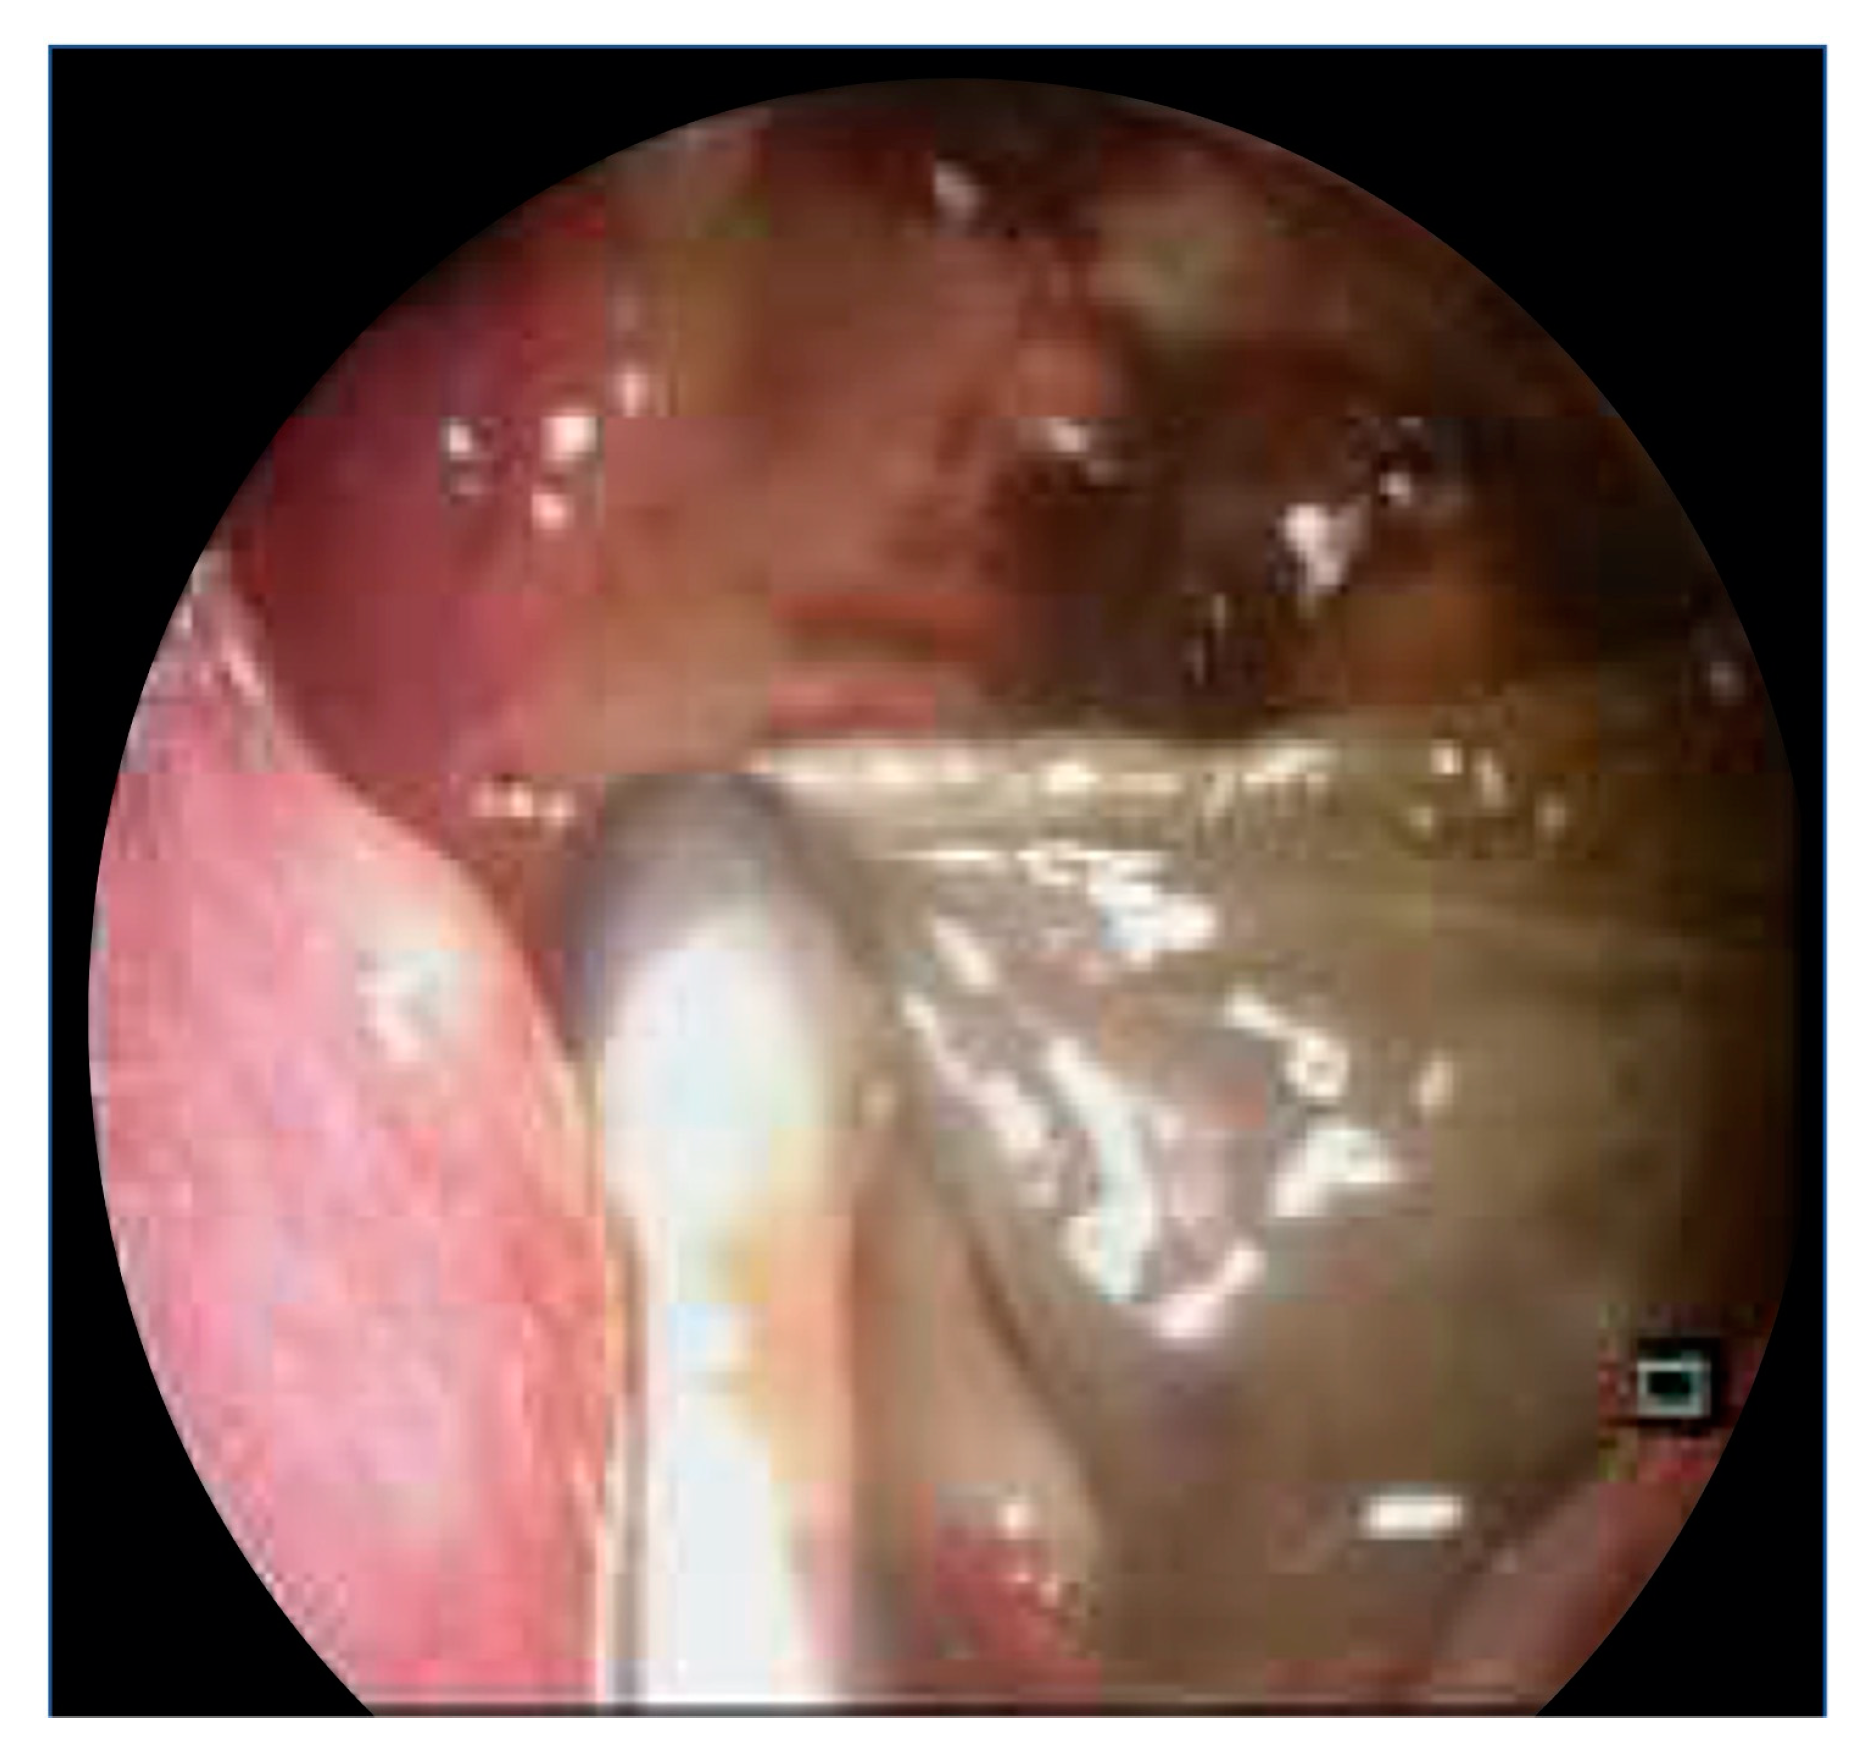

Figure 4.

Endoscopic clinical image depicting intraoperative findings of denuded left maxillary sinus mucosa, with some remnant dusky mucosa.